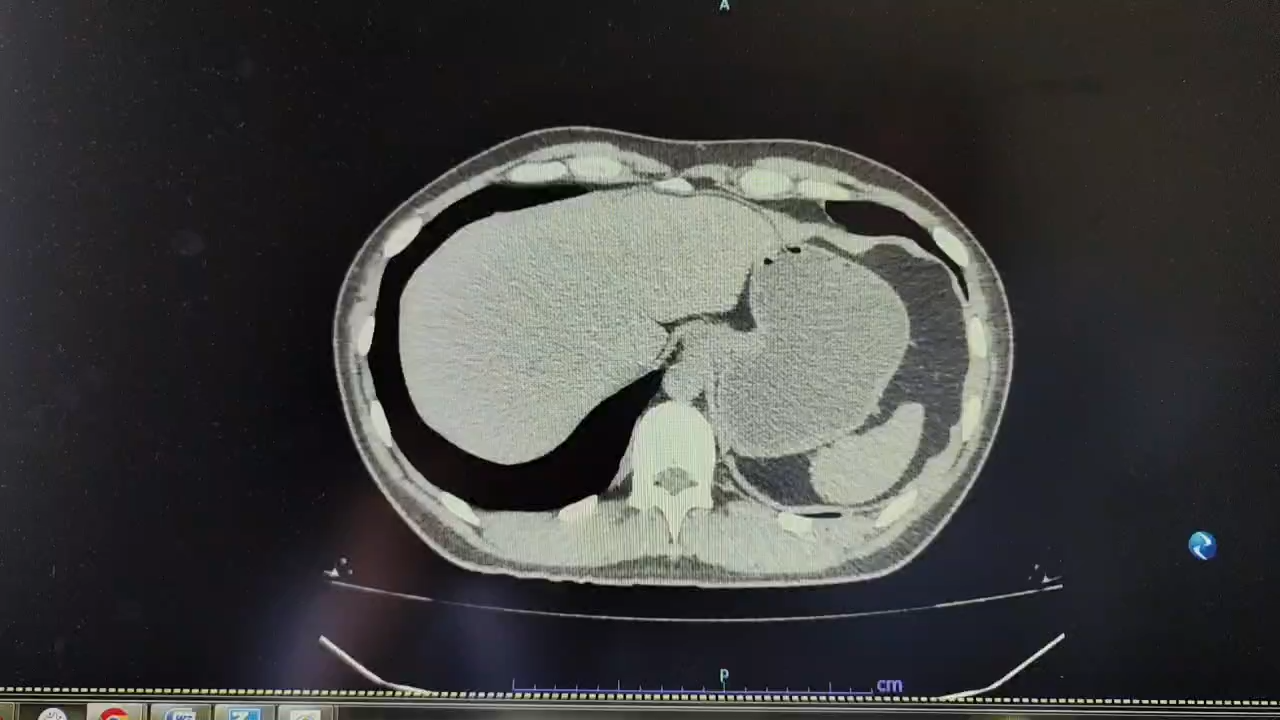

患者急诊入院的腹部CT及之前所做的气腹CT,腹部均无“漩涡征”,表明患者初次全结肠切除及半年后的小肠关瘘手术,虽然造成腹腔广泛粘连,但并没有肠襻的扭转,临床也没表现有肠梗阻症状,所以说这之前是清白的。这种清白包含两层意思,一是无临床意义的肠管扭转梗阻,二是无影像意义的肠管扭转。患者保守治疗无效,梗阻病情加重后,才出现局部肠襻的漩涡征。这表明漩涡征是梗阻后的继发影像,而不是梗阻起病的原发征象。患者急诊粘连松解手术只发现一般性的粘连索带卡压,导致梗阻,并肠襻无扭转的证据。术后患者不幸发生炎性肠梗阻,复查CT,漩涡征已不甚明显。

上述事实表明,漩涡征是急性肠梗阻局部肠管旋转的客观影像证据,但并不等同于临床肠扭转的证据。本例患者梗阻已发生之初,虽有肠襻扩张积气积液,却无漩涡征。梗阻发展病情加重,梗阻近端的肠管进一步膨张 ,有限的腹腔空间迫使其发生继发性旋转,于是就出现了昙花一现的漩涡征。而粘连松解梗阻解除后,虽然再度导致肠梗阻。梗阻的位点变化,漩涡征已不显著。当然我们还期待炎性肠梗阻缓解后的腹部CT结果。